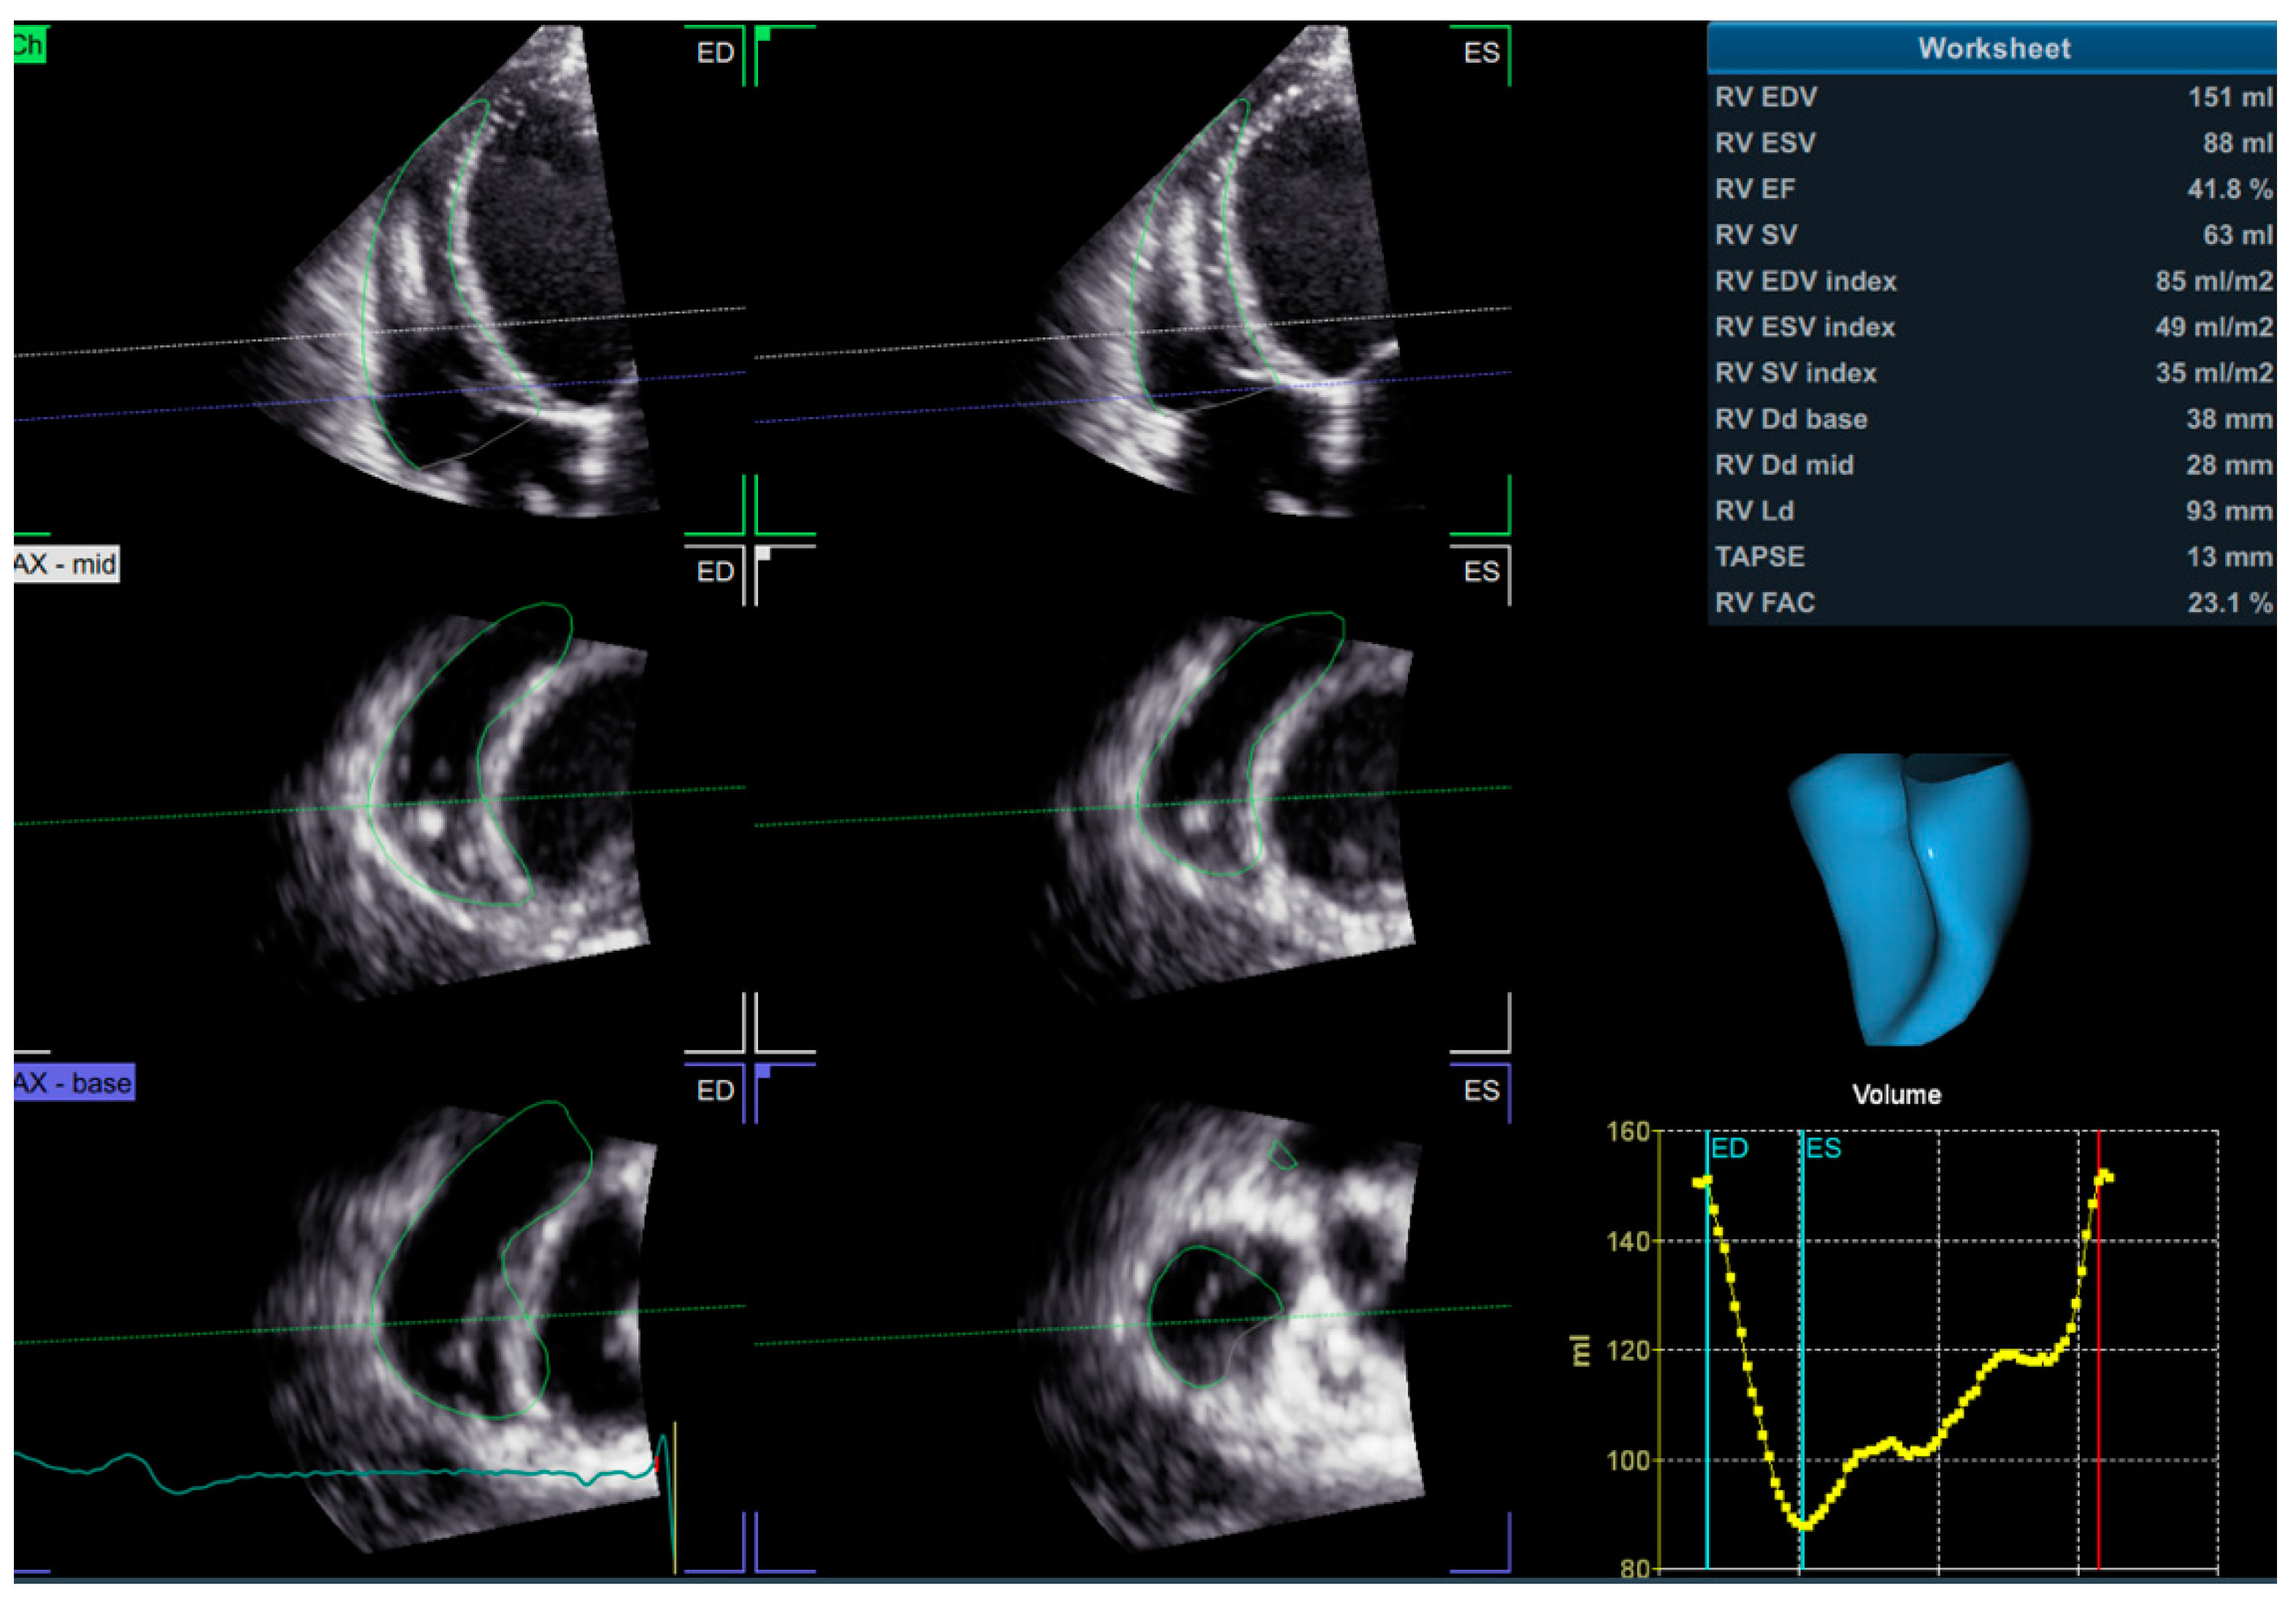

3D echocardiography overcomes the geometric assumptions used in 2D echocardiography. As such, it is particularly useful for the evaluation of the RV, which—due to its complex anatomy—cannot be comprehensively assessed with 2D measurements only. 3D echocardiography integrates both the longitudinal and radial components of RV contraction [30] and, unlike 2D echocardiography, allows the assessment of antero-posterior shortening as well. The images are acquired with a 3D probe from the apical RV-focused view, usually using a full-volume data set and a multi-beat acquisition. The acquired image must include the entire RV volume, from the tricuspid valve to the pulmonary valve, with good temporal and spatial resolution. The data set is subsequently analyzed with dedicated software (Figure 4), by tracing the endocardial surface of the RV, which allows the reconstruction of the RV geometry and the calculation of RV volumes and EF. The 3D RV volumes and EF have been widely validated against the gold standard represented by CMR [74,75,76]. The main limitations of 3D RVEF are load dependency, challenges in correctly tracing the endocardial border, image quality, “stitching” artefacts in the case of arrhythmias, time consumption, and limited availability [30]. A 3D RVEF < 45% is considered abnormal [26].

Figure 4.

3D assessment of RV volumes and ejection fraction using dedicated software. 3D—three dimensional; RV—right ventricle.